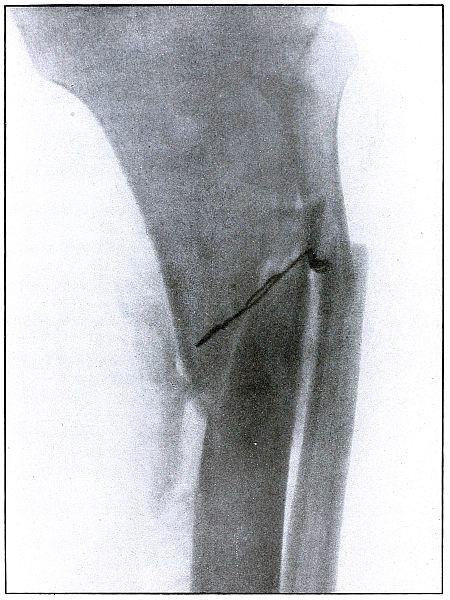

63. Gunshot fracture, tibia 136

64. Gunshot fracture, tibia 138

Plate 63.

_

[Pg 137]

Rifle—Plate 63.

LOWER EXTREMITY.

Gunshot Wound of the Middle of the Tibia,

with Few Large Fragments.

The course of the bullet was transverse from without inward.

The direct impact of the bullet, in high velocity of short range, has produced the typical “X” fracture due to the radiating lines of force.

The wound was infected, as is shown by the drainage tubes in the wound.

The emergency treatment in such cases is simple antiseptic dressing and temporary splint immobilization.

The subsequent treatment is the management of the infection.

The results in such cases are favorable. [Pg 138]